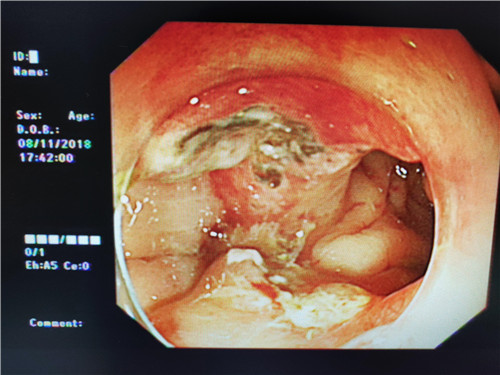

在检查过程中,当曹鹏主治医师将内镜进至吻合口狭窄处时,却偶然发现狭窄部位旁边还有一小小入口,探镜而入,发现这条小小隧道与狭窄部一同通向肠腔,中间相隔了一条不宽不窄的“桥梁”,把本来通畅的“大路”隔成了两条幽径小道,因此患者排便才会堵塞不通。经过反复观察,仔细斟酌后曹鹏医生萌生了,把“桥梁”拆掉,使“曲径小路”变“宽敞大道”的想法。因为这时如果按原计划行肠镜下吻合口扩张术已经没有太大的意义,但肠道薄弱容易造成穿孔,“桥梁”处是否有大的血管,存在出血、穿孔的风险等等,这些都需要与主管医生进一步探讨。随即他与普通外科史和平主任,消化内镜室王莹主任会诊后决定实施“粘膜桥离断术”(ESD内镜下粘膜剥离术)。将术中风险及意外向患者及家属充分告知后,征得患者家属同意签字,随后便开始施行手术。在史主任、王主任、李侠护士长的支持保驾护航之下,曹鹏医生以精湛的医疗技术,与护士的默契配合,顺利完成了手术,术中无出血、穿孔,眼前显示器屏幕上出现了预期中的“宽敞大道”,手术成功了!大家原本绷紧的面容出现了笑容。患者从此以后不会再有排便不畅的痛苦了,患者唐某及家属,欣喜及感激之情溢于言表,医生们再一次为他解决了一件大事情,患者术后恢复良好。

这次手术从发现到术式的改变,体现了当下微创治疗的优势,在内镜下可以完成形式多样的创伤小,恢复快的的手术。目前,内镜下微创治疗正在以突飞猛进的速度发展,势必为广大患者带来更大更多的福音。